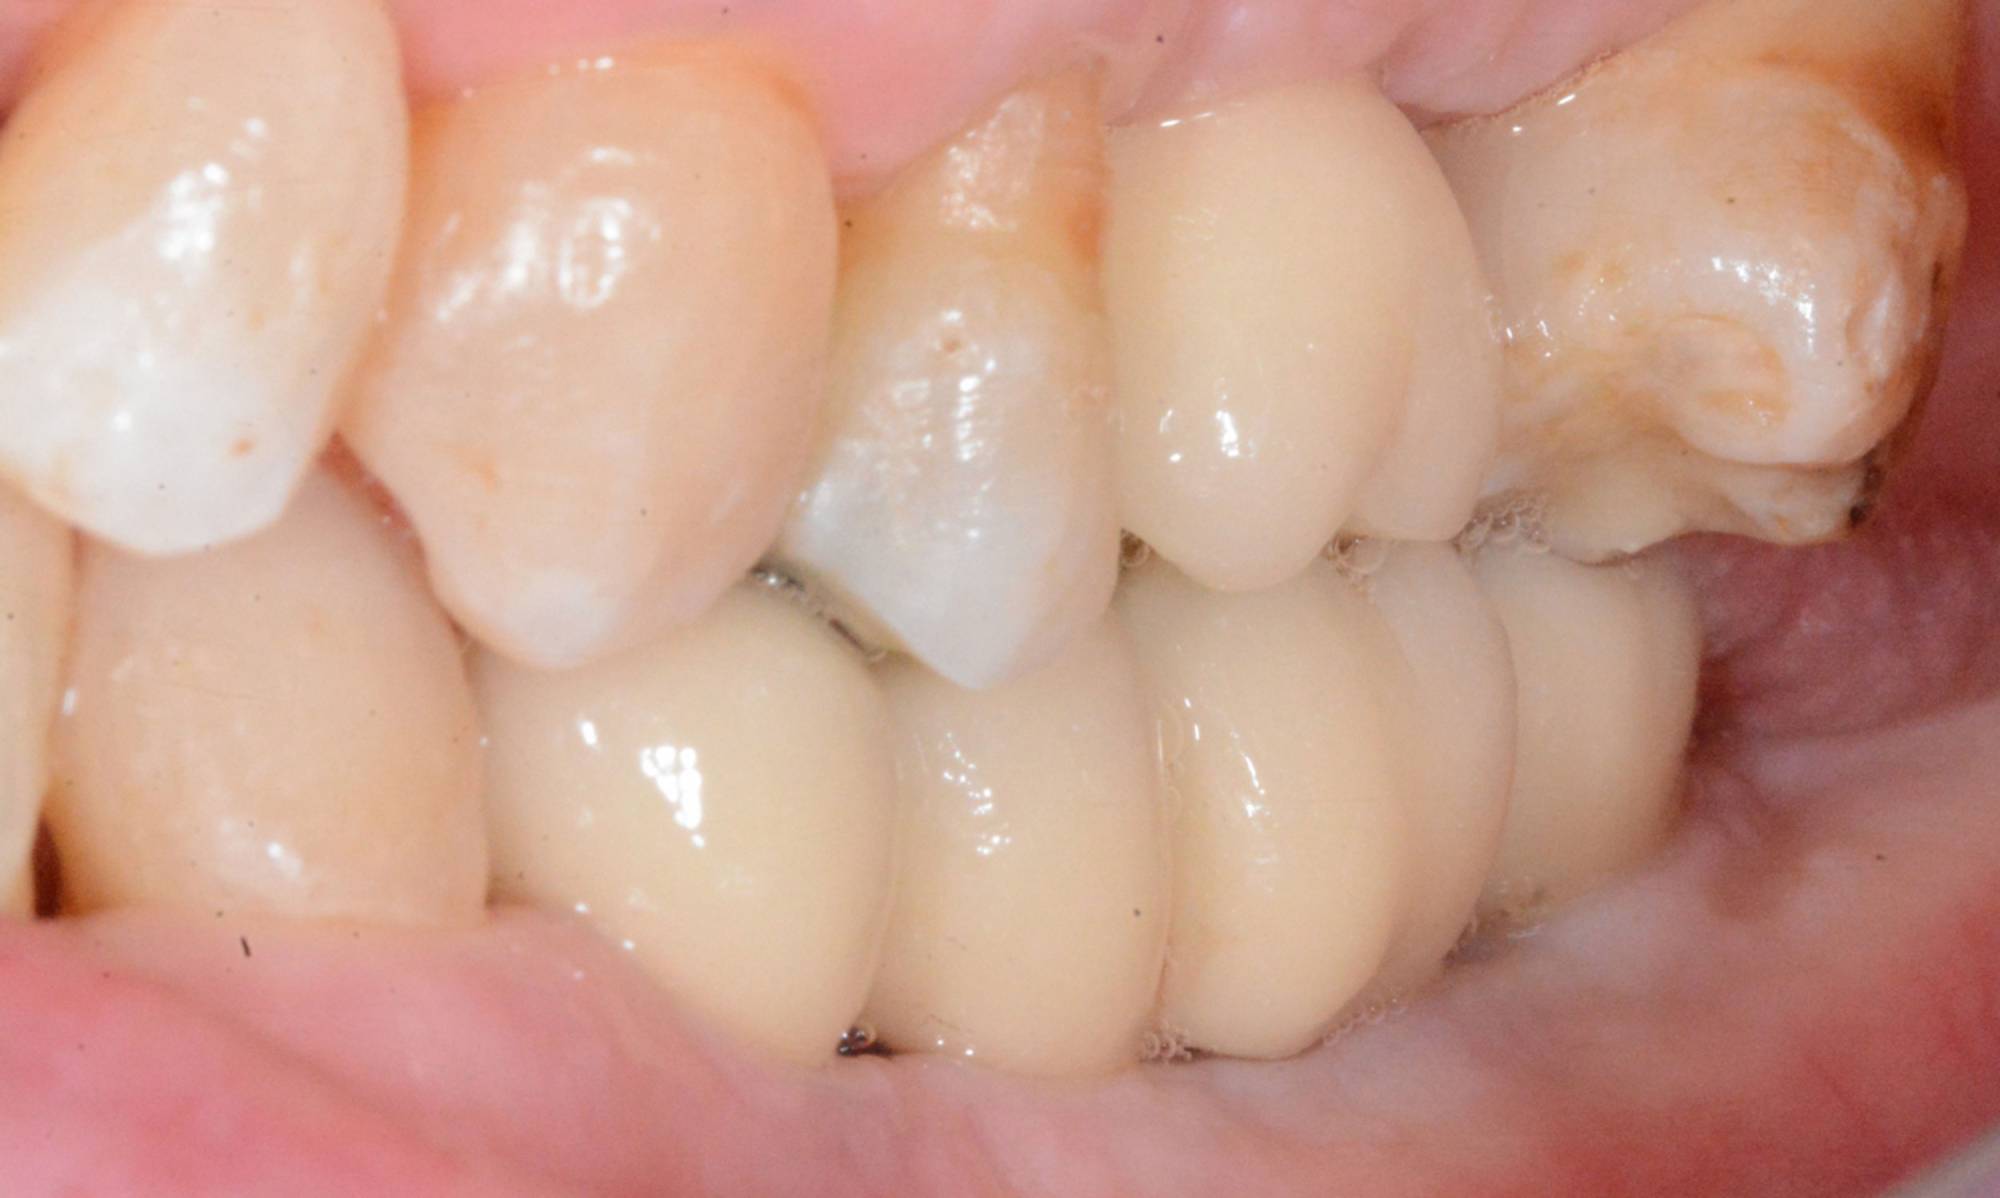

L'impianto, oltre a essere un metodo sicuro, garantisce l'aspetto esteriore e la piena funzionalità di un dente naturale. Oltre a ciò, mantiene l’integrità dell’osso, non va ad intaccare i denti adiacenti - come invece farebbe un ponte - e migliora l’estetica facciale prevenendo la perdita ossea.

Gli impianti sono molto versatili e possono essere usati per sostituire un dente singolo, più denti fissi o addirittura un'intera arcata. Inoltre, possono essere inseriti sotto una protesi mobile per stabilizzarla migliorandone il comfort.